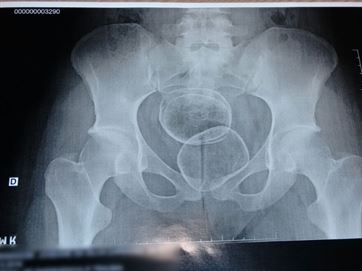

“Ela foi encaminhada para o Hospital de Trauma, onde fez exame de raios-X, que constatou a droga introduzida”, disse David, explicando que o entorpecente estava dividido em três pacotes.

A jovem, que alegou que a maconha seria direcionada a um companheiro que é detento da unidade prisional, foi detida em flagrante e conduzida à Central de Polícia Civil da Capital, no bairro do Geisel, na Zona Sul da cidade. A droga apreendida foi encaminhada para perícia.